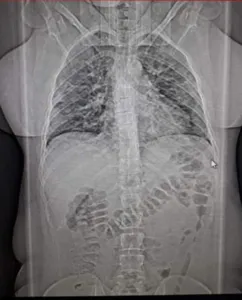

Autor Na foto, tomografia dos pulmões da sobrinha, com 60% de infecção - Foto: Arquivo pessoal

Enfim, a consulta. Suspeita de trombose. A tomografia apontou 60% dos pulmões comprometidos; os exames de sangue revelaram outras mazelas. A ordem era interná-la urgente. Eis a encruzilhada. Hospitais com corredores apinhados. Leitos, nem se cogitava.